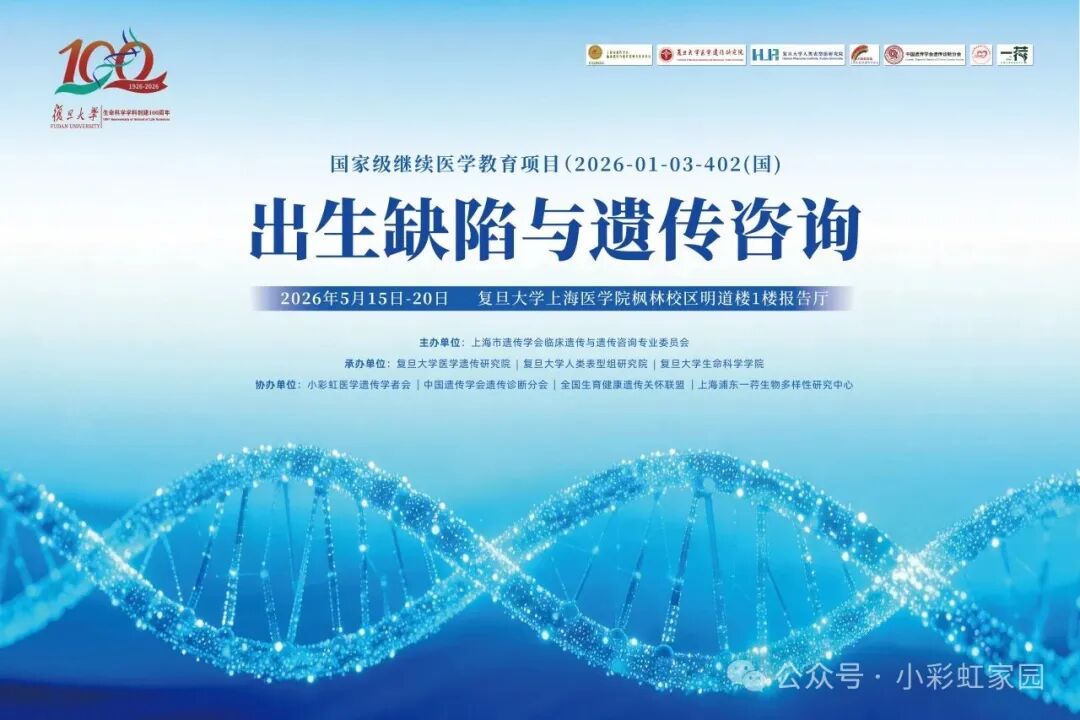

最后通知!2026年国家级继续医学教育项目:出生缺陷与遗传咨询学习班暨复旦大学遗传咨询攀登论坛第六期